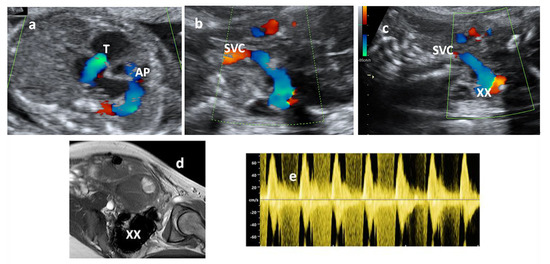

2. Case Report